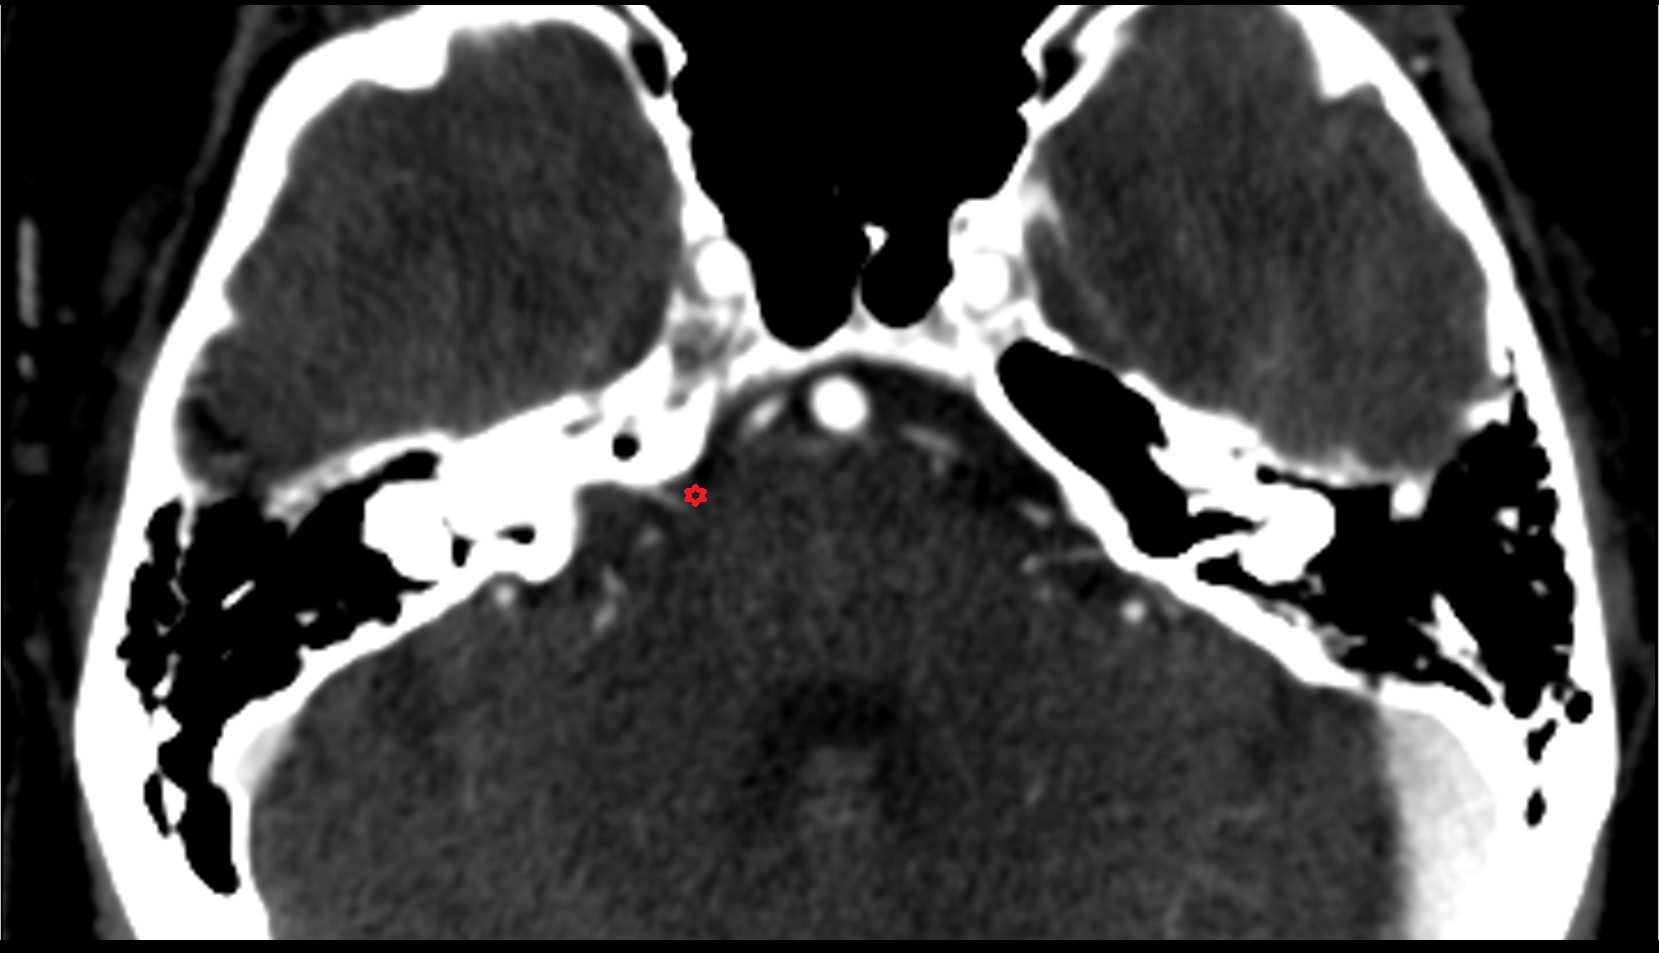

- Cerebellopontine cistern